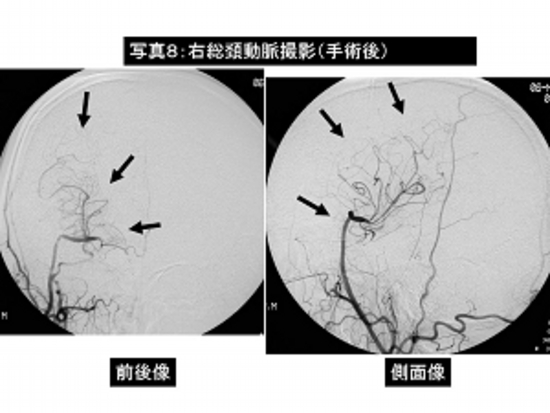

写真8:右内頸動脈閉塞症に対して左橈骨動脈を利用した頭蓋外—血管頭蓋内血管バイパス術(右総頸動脈—橈骨動脈グラフトー右中大脳動脈吻合術)の術後脳血管撮影。

バイパスを介して頭蓋内に良好な血流が確認されます(→)。

患者さんは特に症状はなく自力歩行で退院されました。